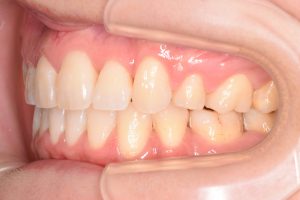

初診時(2022年12月)と装置撤去時(2025年9月)の写真です。

右側

左側

・叢生

・右上犬歯低位唇側転位

・下顎骨の後方位による上顎前突

・下顎前歯部唇側傾斜

・右側第二大臼歯部シザーズバイト

両側の犬歯が咬みあっていないので

奥歯にとても負担のかかる咬合状態でした。